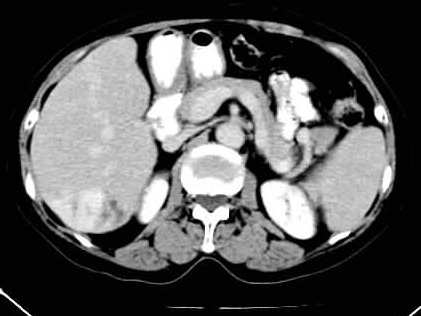

标题: CT24035:肝内占位

右叶后段血管瘤,层面少,看不见左叶,脾大。

血管瘤、肝左叶缺如、脾稍大。

1)肝右叶后段血管瘤。2)脾大。

肝右叶后段血管瘤、肝左叶缺如、脾大

肝右叶后段低密度块影,增强后造影剂逐渐向病灶充填,支持肝血管瘤。